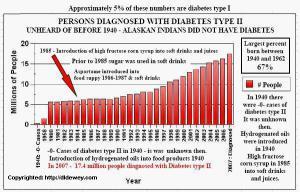

Between 1975 and 1984 most soda manufacturers switched from sugar to high-fructose corn syrup because of price. You may find the correlation between the rapid rise of obesity and the introduction of soft-drinks with HFCS interesting (see figure below). In addition, there is a disturbing correlation between diabetes and the use of HFCS (below). Close to 70% of the packaged foods found on grocery store shelves are manufactured with HFCS or hydrogenated fats. Even the price of beef is artificially low because they are fed an unhealthy diet of subsidized grains instead of their natural meal of grass. The cattle are given doses of antibiotics to keep them from getting too sick for meat processing.